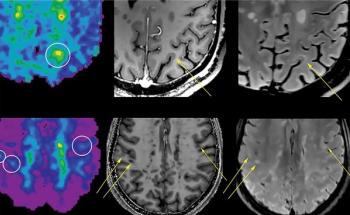

New research suggests that an emerging predictive biomarker, derived from a combination of magnetic resonance imaging (MRI) brain scans and a machine learning algorithm, has significantly greater accuracy than previously established measurements for diagnosing Alzheimer’s disease.